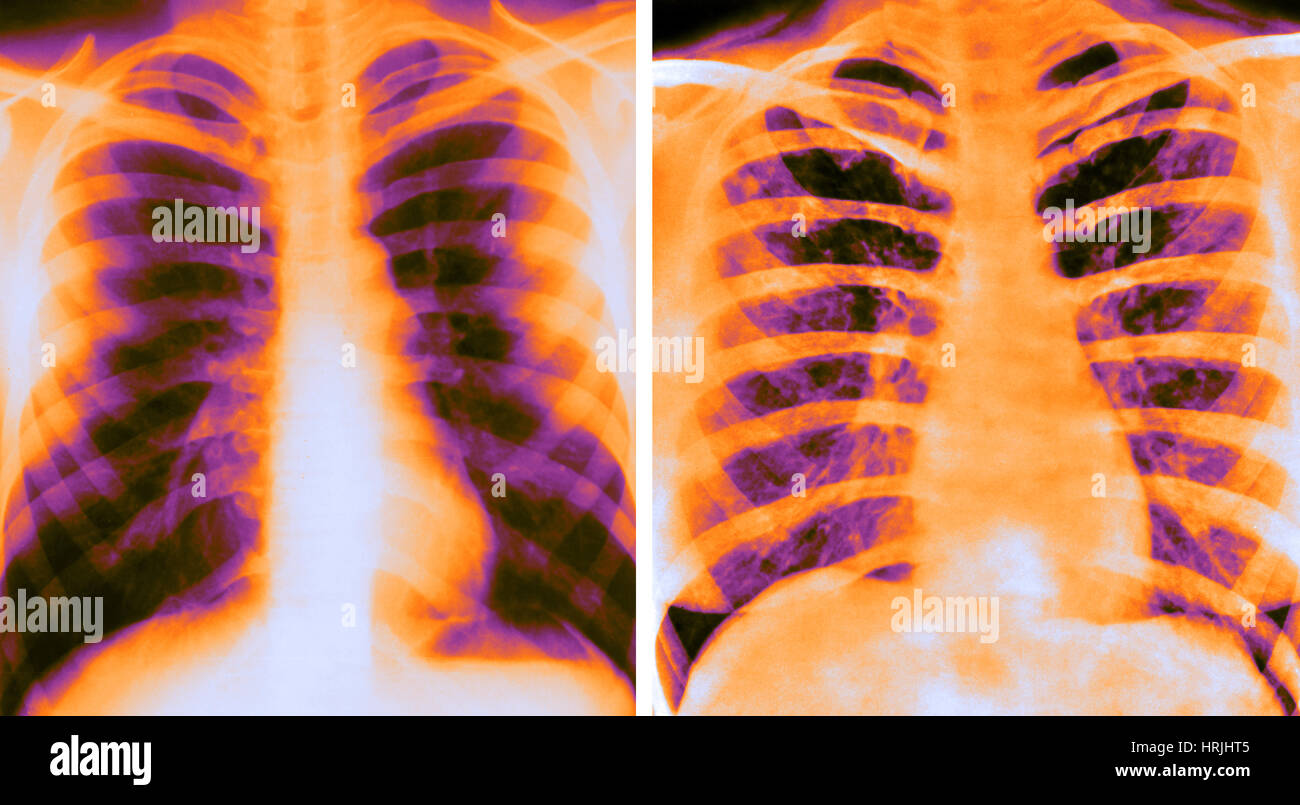

From fineartamerica.com

Coloured Xray Showing Lung Cancer Photograph by Simon Fraser/science What Color Should Lungs Be On X Ray 5 when the patient inspires. cxrs should always be taken during maximum inspiration to allow visualization of any pulmonary abnormalities. Not quite black, because there is still tissue there, but still quite dark. Airway, breathing, cardiac, diaphragm and everything else. darker colors indicate less dense material, and lighter colors indicate more dense material. This web page covers pa. What Color Should Lungs Be On X Ray.